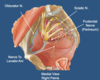

Label all:

Largest nerve passing through the greater sciatic foramen:

- sciatic nerve (L4-S3). Joins with the lumbosacral trunk before exiting.

Route of lumbosacral trunk to it union with the sciatic nerve:

crosses over pelvic brim

Somatic nerves making up the lateral component of the pelvic neurovasculature are the:

- obturator nerve, sciatic nerve, and pudendal nerve.

- Lumbosacral trunk passes over the pelvic brim to unite with sciatic.

Label all: